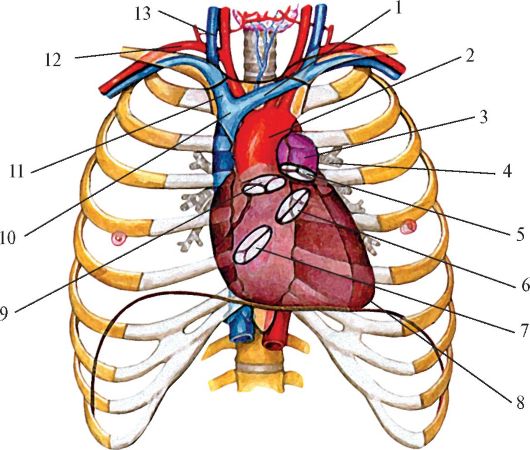

Анатомия Сердца: Расположение и Функции